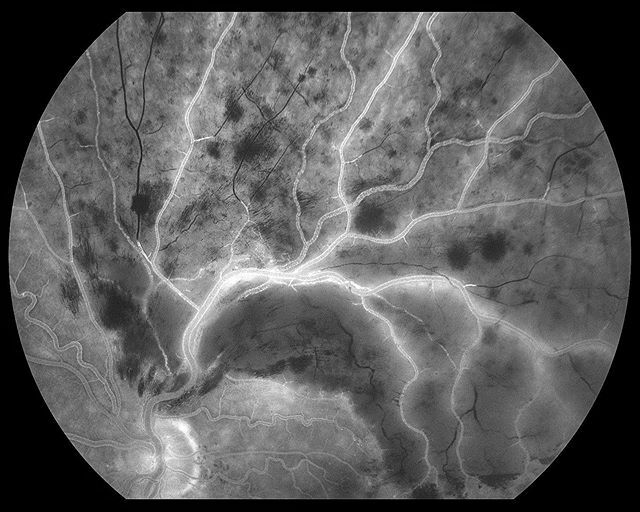

February 2017 issue of @aaoeye

@aaojournal Ophthalmology. This is the fluorescein angiography image of the case I posted most recently. What’s the diagnosis? A) Bartonella neuroretinitis B) Branch retinal vein occlusion C) Coat’s disease • •• •••… https://ift.tt/385rr3k pic.twitter.com/MnYKIuPQ5I